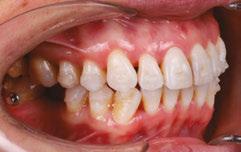

Patient S.T., age 32, presented in the hope of creating a radiant smile and a functional bite. She had been dealing with dental problems all her life. Her X-rays exhibited multiple direct restorations as well as endodontic treatment. Due to the loss of her molars, her teeth had shifted considerably over the years. Her dentist recommended she see us to create a pleasing smile and to rehabilitate her occlusion for future prosthetic treatment (Figure 8).

Diagnosis

The patient’s occlusion was super CL I on the left and CL II on the right. Both arches showed slight constriction with lower anterior crowding. Her smile arc was canted, and both midlines were shifted in opposite directions. On cephalometric

Figure 7: Case 1 progress to date — 4 months (left) and 10 months (right)

Figure 8: Case 2 initial records

Case discussion

analysis, her ANB was 5.84, and IMPA was 102.64, both representative of skeletal Class II with incisor proclination. There were two long-standing extraction sites into which the UR6 and UL6 (partial) had supraerupted. Her thin gingival mucosa posed a challenge in keeping the roots in the bone, so treatment had to be planned correctly and executed gradually to maintain her gingival architecture.